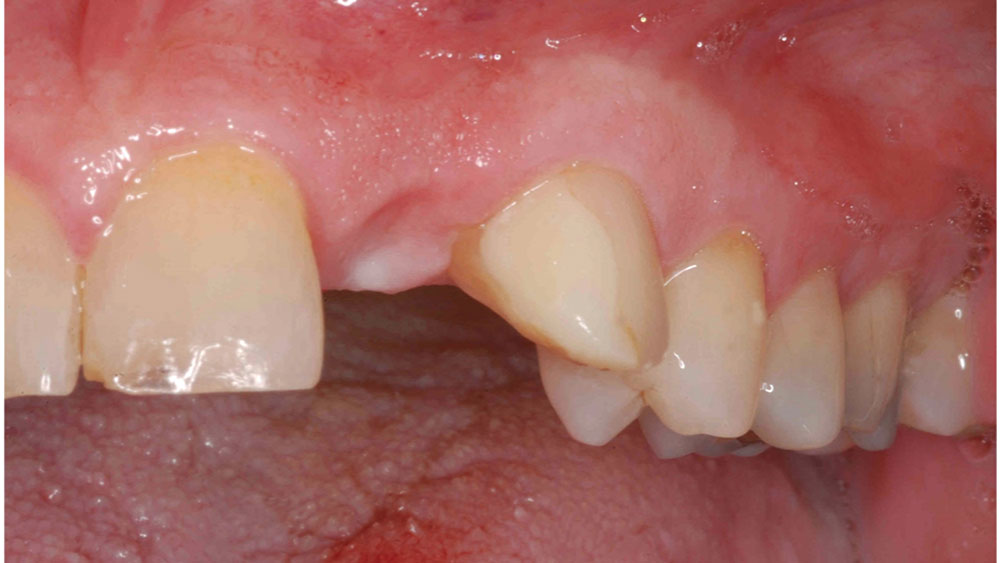

For the first few anterior cases, you should select clinical situations in which an untreatable tooth is removed, the extraction site is grafted, and the implant is placed after several months of healing. This approach allows you to develop the ideal soft-tissue contours and bone volume needed for straightforward implant surgery and a predictable outcome. Until you have more experience, I would not suggest extraction with immediate implant placement — unless you have Dr. Jack Hahn standing by your side! It’s also important to select patients who have favorable teeth alignment as well as a thick tissue biotype, both of which make it easier to achieve a natural emergence profile and esthetic result. High smile lines should be avoided.

This case is an example of an ideal clinical situation for dentists who are new to placing implants in the esthetic zone. The patient requested treatment for a fractured upper lateral incisor. After extraction, grafting and healing, ample bone and soft tissue were present, and an implant was placed in optimal position for an esthetic result. The screw-retained restoration predictably restored form and function, illustrating the beautiful results that can be achieved by observing simple surgical and prosthetic guidelines.